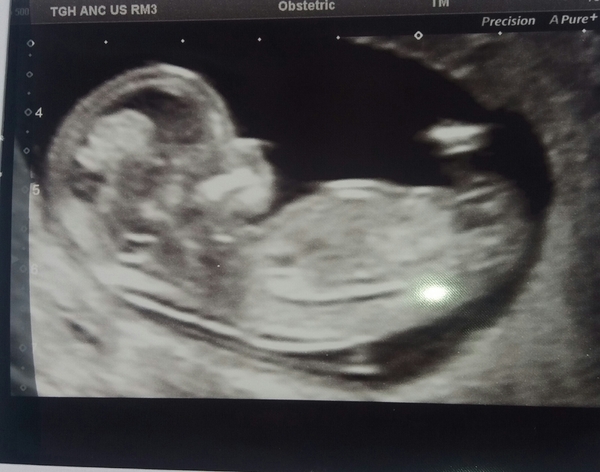

ew1990 · 01/09/2020 16:19

Hi ladies. It went well. Measuring a day behind at 12+4 but baby was curled in a ball so had to do a lot of shaking to get that measurement lol. Managed to stretch out at the end and could see arms waving about. I nearly cried I'm so relieved.

Due date 12th March.

Hopefully I'll relax a bit now. I was so nervous and the lovely sonographer gave me my picture for free. It's £4 a picture at our trust.

@ew1990 That’s a nice pic! I think it’s only free as partners aren’t allowed. I got given 2. With DS I paid £5 for a crappy pic then again for the next scan.